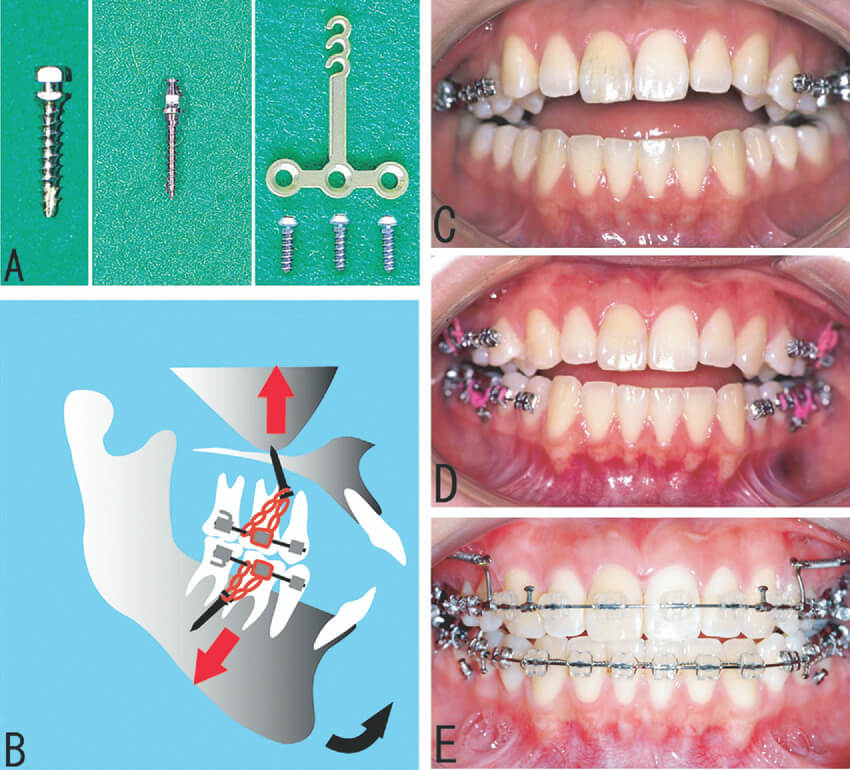

「我只是做矯正,要打釘子進去也太可怕了吧!」當進行矯正療程,初聽到骨釘這個詞,讓您疑惑又害怕嗎?顧名思義,骨釘是一種大約 8-10 mm 的小螺絲釘,可鎖在牙床上形成錨點,協助拉動牙齒,是矯正時很常見的輔助工具。

什麼情況下會使用骨釘呢?一般來說,齒列過度凌亂、上下顎骨太突出如暴牙、戽斗等,都有可能使用骨釘輔助治療,需經由牙醫師專業評估,才能判斷適當的使用時機。

如同前面所說,較複雜或需要較大幅度推動牙齒的案例,在牙醫師的評估之下很可能會使用骨釘。骨釘提供錨定輔助矯正器施力,讓拉動牙齒更有效率。

那麼,只有傳統矯正才會使用骨釘嗎?答案是不一定!無論是傳統矯正或隱形矯正,骨釘都能達到輔助效果,尤其隱形矯正屬於溫和漸進的矯正方式,當矯正所需的移動力道可能超過隱形牙套的控制範圍,這時配合骨釘就可以獲得更好的療效。故千萬不要因害怕而排斥使用骨釘,它其實是矯正常常不可或缺的利器呢!

讓我們先由材質開始了解,骨釘大多為生物相容性高的鈦合金所製成,發生過敏或發炎的機率不高。再者,骨釘體積並不大,長度約為 8-10 mm,傷口很小,大約1週左右就會癒合。